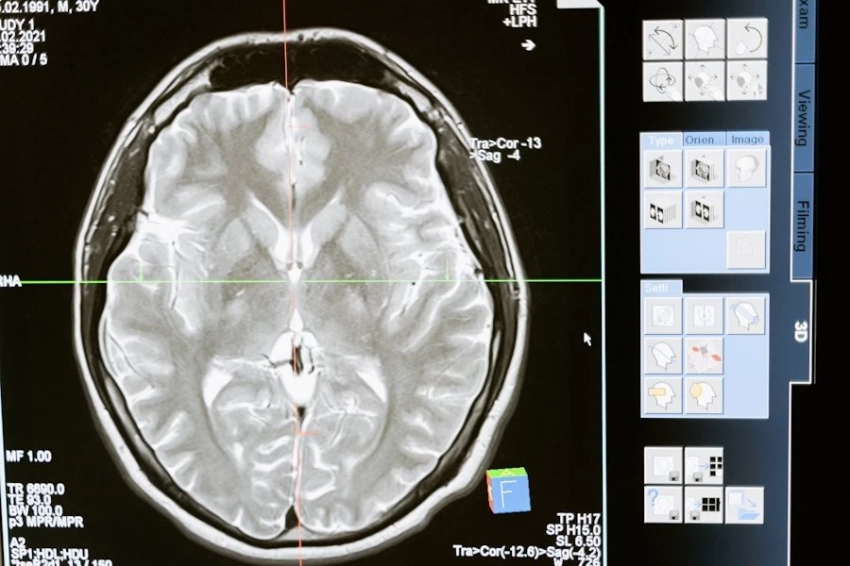

Исследователи провели серию экспериментов на мышах с ожирением и обнаружили, что определенные нейроны в головном мозге, которые производят белок SF1, могут снижать воспаление в белой подкожной жировой ткани. Эти нейроны расположены в гипоталамусе, области мозга, ответственной за регуляцию голода и метаболизма.